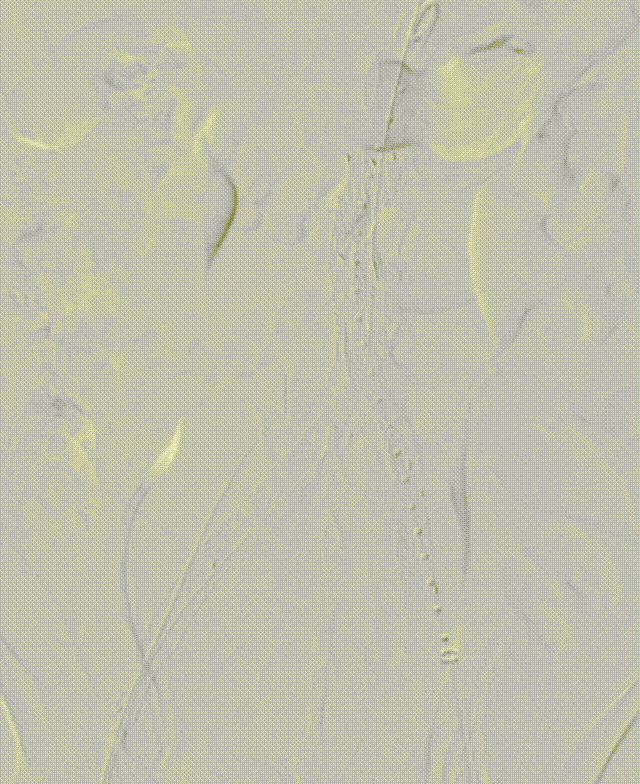

6.将右侧球囊往上输送至高于肾动脉的位置以留出空间进行支架输送等步骤,因血流湍急,球囊未能实现在理想位置的展开以进行近端血流阻断

7. 重新送入左侧球囊至右侧球囊远端,对右侧球囊内造影剂进行小部分回抽,使左侧球囊通过球囊与血管壁的间隙继续往近端输送,充盈左侧球囊使其部分展开,捏住左侧球囊输送杆,维持左侧球囊位置,降低右侧球囊受到的血流压力。

8. 将右侧球囊继续往近端推动,超过肾动脉以及经左锁骨下动脉预置的造影椎管,充分使球囊充盈阻断血流,此时能实现右侧球囊在高于肾动脉的理想位置固定。

gore医疗怎么样「漫腹精论」髂合时宜 精益求精——双MOB球囊导管辅助腹主动脉覆膜支架急诊治疗破裂巨大髂动脉瘤_https://www.jmylbn.com_新闻资讯_第18张

gore医疗怎么样「漫腹精论」髂合时宜 精益求精——双MOB球囊导管辅助腹主动脉覆膜支架急诊治疗破裂巨大髂动脉瘤_https://www.jmylbn.com_新闻资讯_第19张